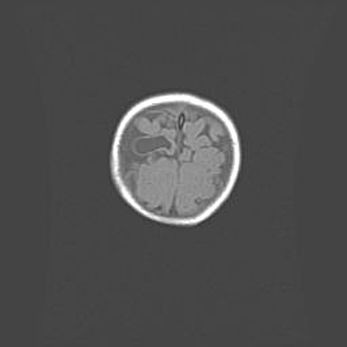

Открытая гидроцефалия.

Возраст: 6 месяцев 15 дней

Вес: 6200 г

Пол: женский

Окружность головы: 41 см

Срок гестации: 38 недель

Гидроцефалия головного мозга у новорожденных – это скопление избыточного количества цереброспинальной жидкости в головном мозге. Ее избыточное скопление в мозге приводит к патологическому расширению желудочков мозга (четырех полостей, расположенных в глубине белого вещества мозга, заполненных цереброспинальной жидкостью и связанных узкими проходами).

Открытый тип гидроцефалии (сообщающаяся) наблюдается тогда, когда нарушен механизм всасывания ликвора в системный кровоток. При этом типе причиной заболевания чаще всего является перенесенные ранее инфекции (например: менингит),  либо же наличие крови в субарахноидальном пространстве.